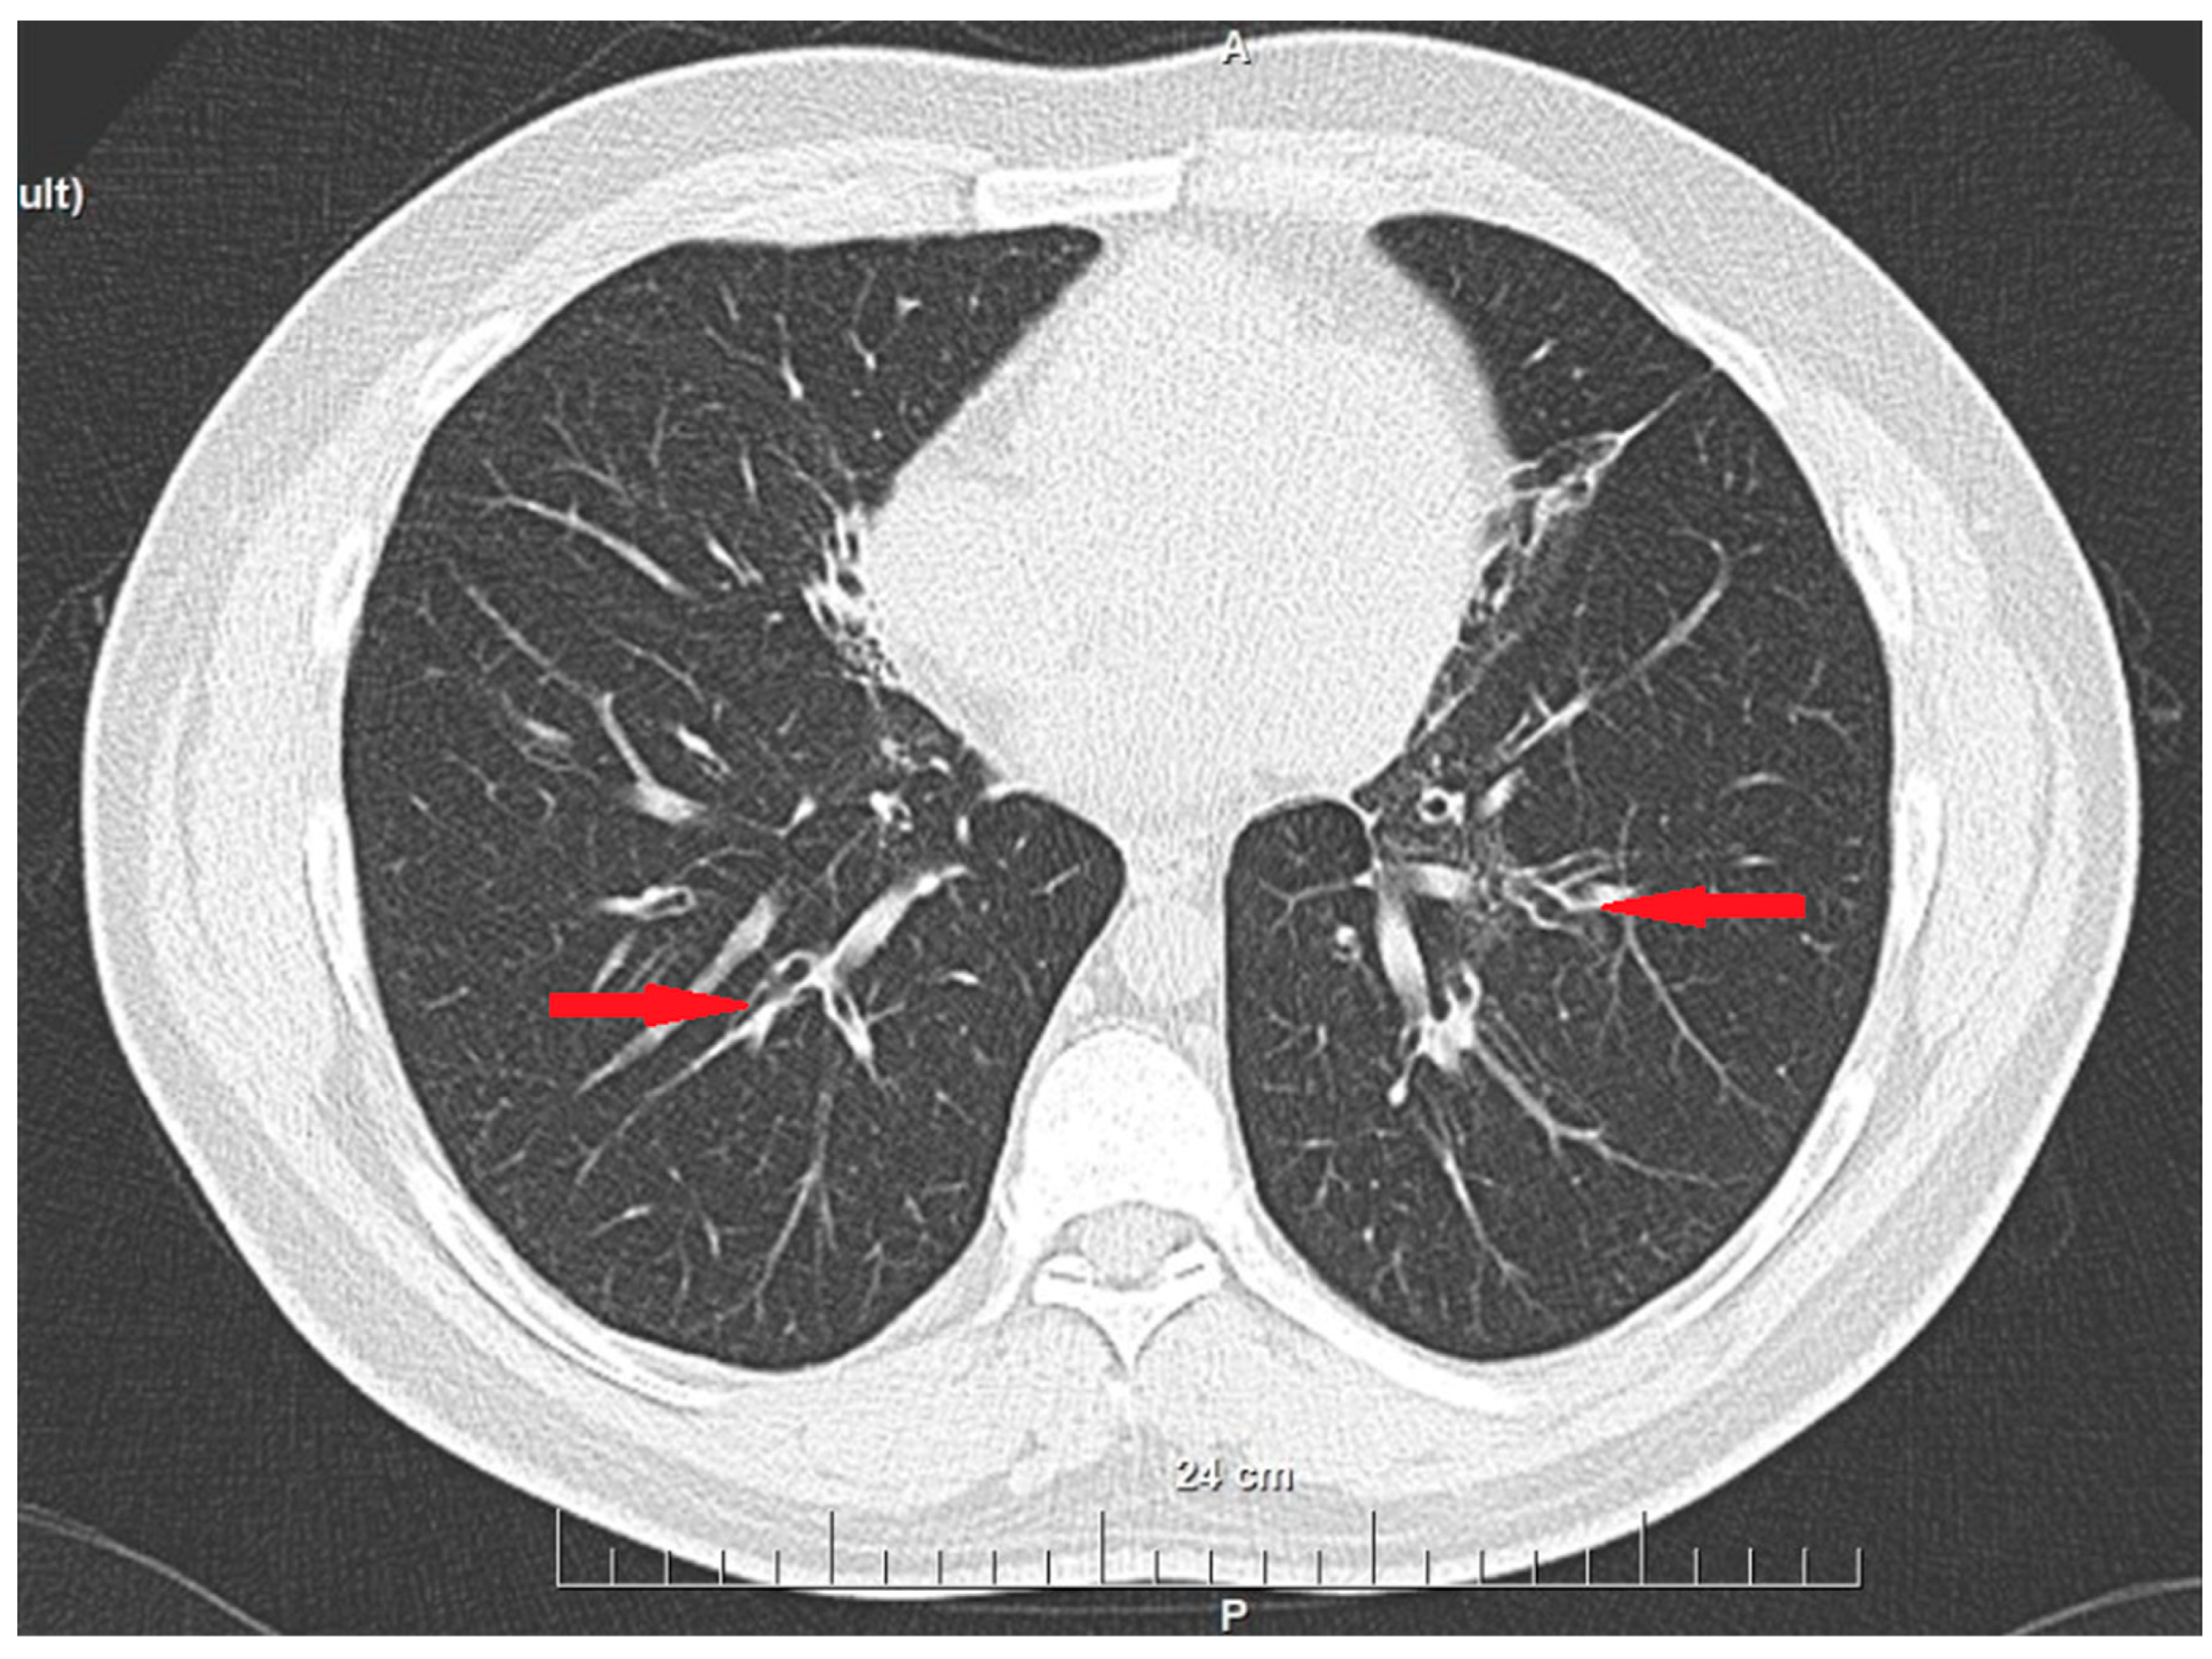

2. Case History